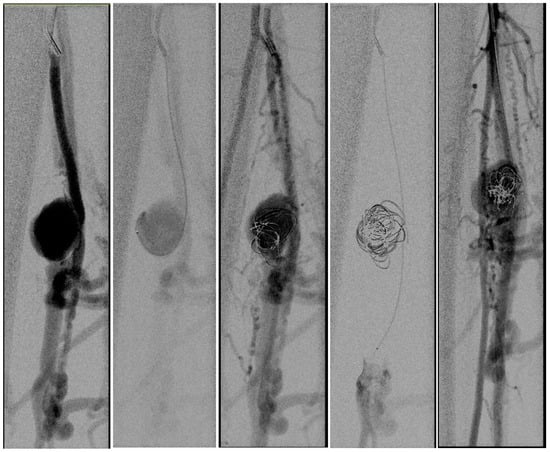

A 31-year-old man presented with calf pain in the right limb which had gradually increased in severity over the previous few months. The pain was throbbing in nature and was not associated with walking. There was a history of war injury to his lower leg in the region of the pain. The patient reported being hit by bomb shrapnel in the lower leg region. Physical examination revealed a pulsatile, tender mass in the mid-calf region. Duplex ultrasound revealed an aneurysm in the mid-calf region of the posterior tibial artery. To define the morphology of the aneurysm and the anatomy of the crural vessels, a CT angiogram was obtained. This confirmed the presence of an aneurysm of the PTA associated with an AV fistula to the deep posterior tibial veins (Figure 1).

Figure 1.

The CT angiogram shows the aneurysm of the posterior tibial artery with AV fistula (contrast uptake by the deep and the superficial veins).